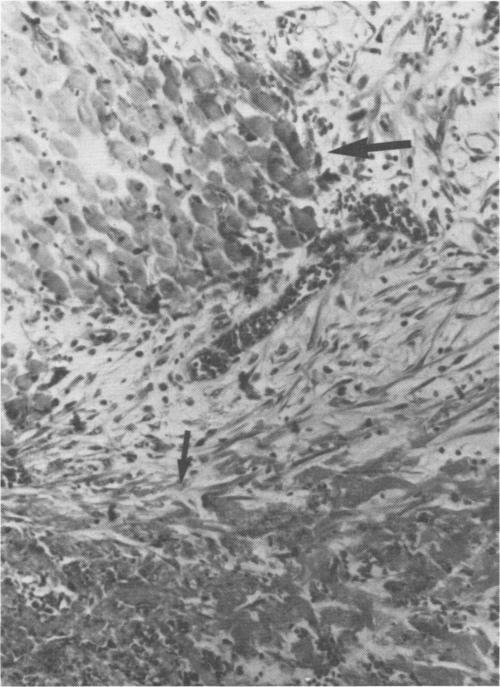

The use of polyglycolic acid (PGA) stretchable mesh applied to the experimentally injured canine spleen can achieve satisfactory immediate hemostasis by tamponade and simplifies the use of sutures to control remaining areas of hemorrhage. PGA mesh with 1/4" and 1/8" openings was utilized for splenorrhaphy in 12 adult mongrel dogs subjected to sharp splenic trauma. By gross and histologic examination, the PGA mesh material appears to undergo progressive absorption to complete absorption by 85 days. For the 12 animals and 30 operative procedures the only complications of the use of the mesh were the occurrence of an intrasplenic seroma in a single animal at 6 weeks after operation and three wound infections. With this material, rapid, simple canine splenic injury repair can be achieved. PGA mesh further assists in the healing process, and in maintaining maximum splenic architecture and function. The material used in this study was manufactured and supplied by Davis & Geck, American Cyanamid, Danbury, Connecticut.

将聚乙醇酸(PGA)可拉伸网片应用于实验性损伤的犬脾脏,通过填塞可实现令人满意的即时止血,并简化了使用缝线控制剩余出血区域的操作。采用具有1/4英寸和1/8英寸网孔的PGA网片,对12只遭受锐性脾创伤的成年杂种犬进行脾修补术。通过大体和组织学检查,PGA网片材料似乎会逐渐吸收,至85天时完全吸收。在这12只动物的30次手术操作中,使用网片的唯一并发症是1只动物在术后6周出现脾内血清肿,以及3例伤口感染。使用这种材料,可以快速、简单地完成犬脾损伤修复。PGA网片进一步有助于愈合过程,并维持脾脏的最大结构和功能。本研究中使用的材料由位于康涅狄格州丹伯里的美国氰胺公司戴维斯&盖克分部制造和供应。